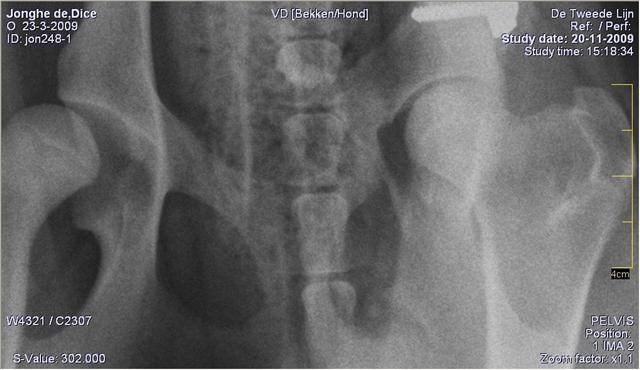

Controle foto van vorige week hier is erg goed te zien dat de op de foto de rechter kant er erg mooi in zit. en dat de andere kant er gewoon uithangt je kunt het ook horen als je wandeld want dan schuift hij met zn nagels over de grond als hij een stap zet, dan ligt de heup eruit. van cindy

> Controle foto van vorige week hier is erg goed te zien dat de op de foto de rechter kant er erg mooi in zit. en dat de andere kant er gewoon uithangt je kunt het ook horen als je wandeld want dan schuift hij met zn nagels over de grond als hij een stap zet, dan ligt de heup eruit.